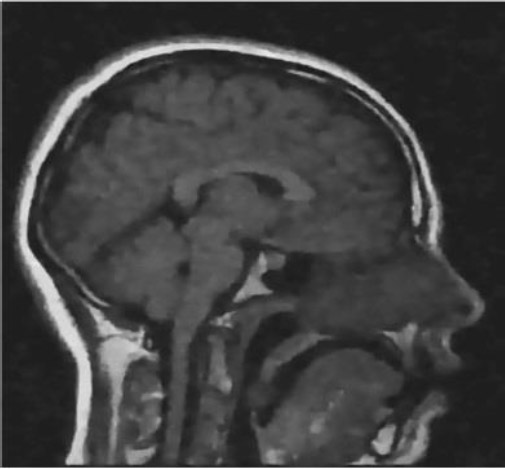

4.7. Clinical Impact After Denoising

To demonstrate the clinical importance of denoising, a comparison is made between noisy and denoised sagittal T1-weighted MRI images. The noisy image may be difficult to diagnose due to its grainy texture and low contrast of tissue structures, as significant structures, such as the brain stem, thalamus, and corpus callosum, are obscured. These make a lot more sense post-denosing, enabling the assessment of subcortical integrity, the inspection of ventricular pathways, and the secure differentiation of gray and white matter. These improvements are not limited to visual interpretation; their direct application to early detection and treatment planning of diseases such as hydrocephalus, multiple sclerosis, and brain tumors firmly places them within the medical field.